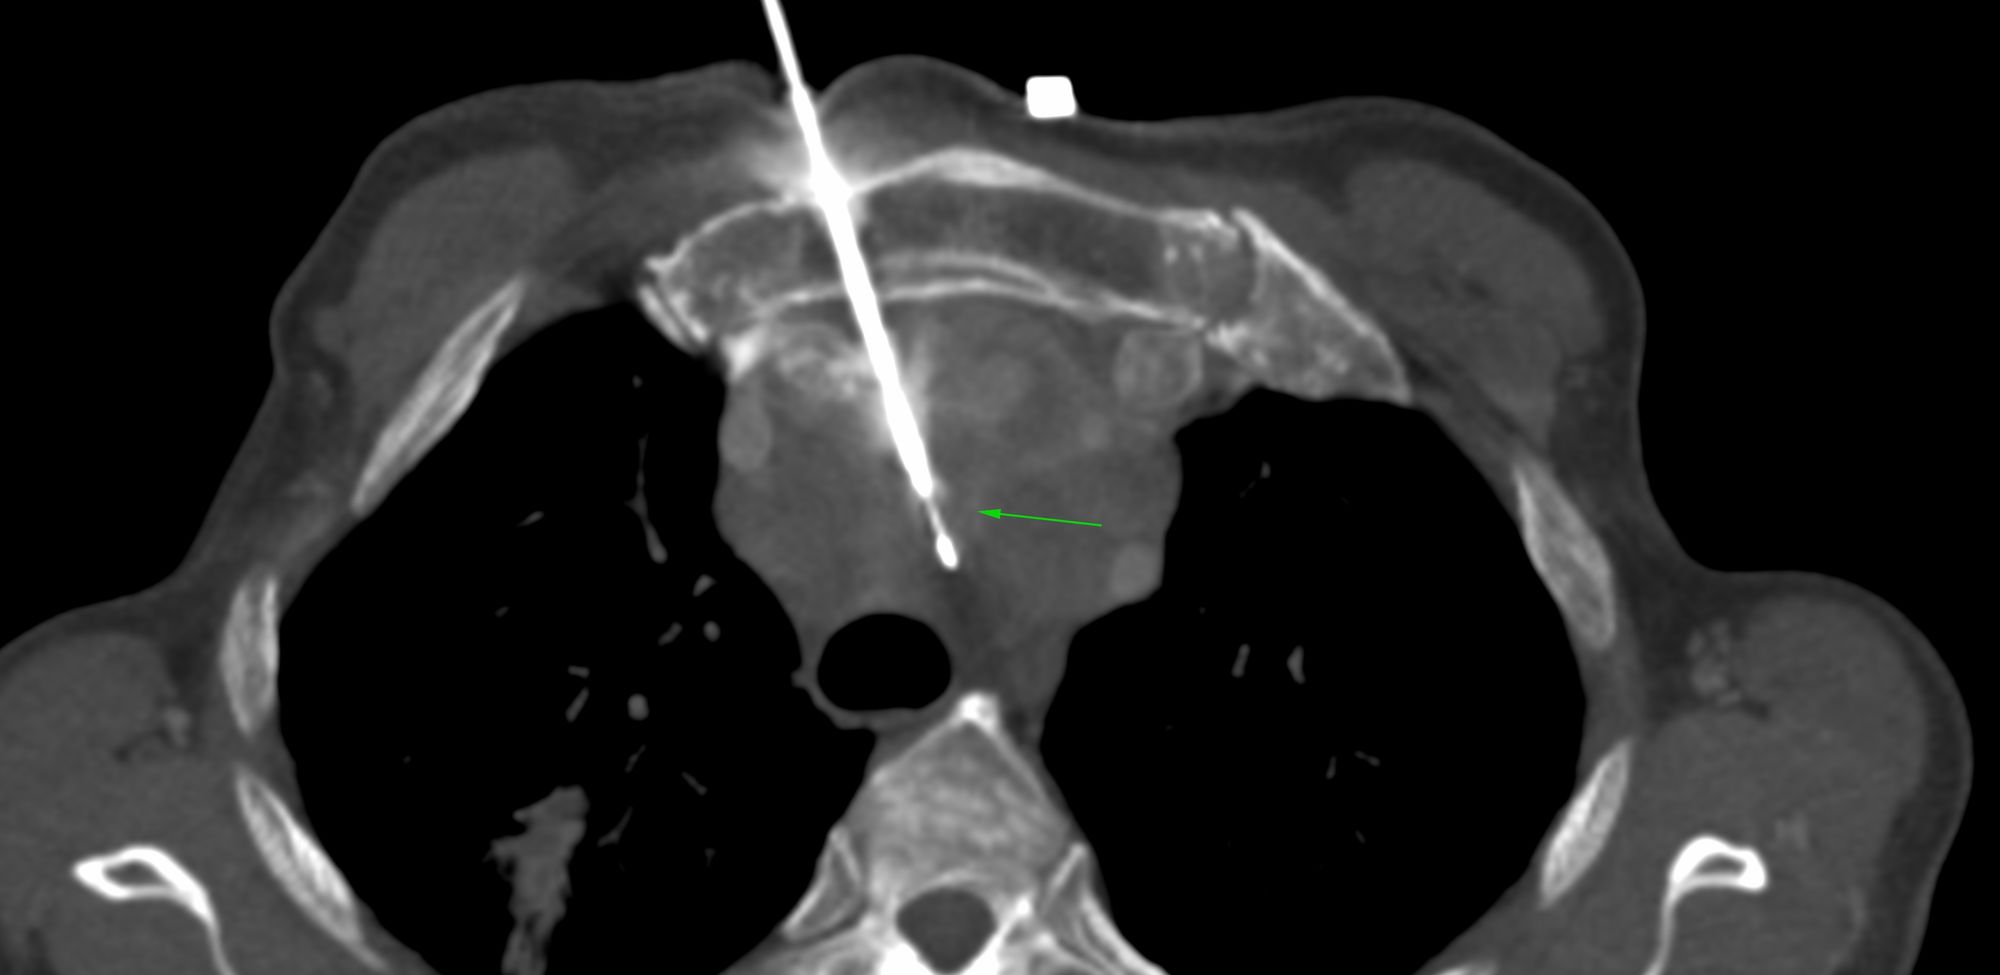

Case 124: Left Para-Aortic Posterior Mediastinal Node Biopsy